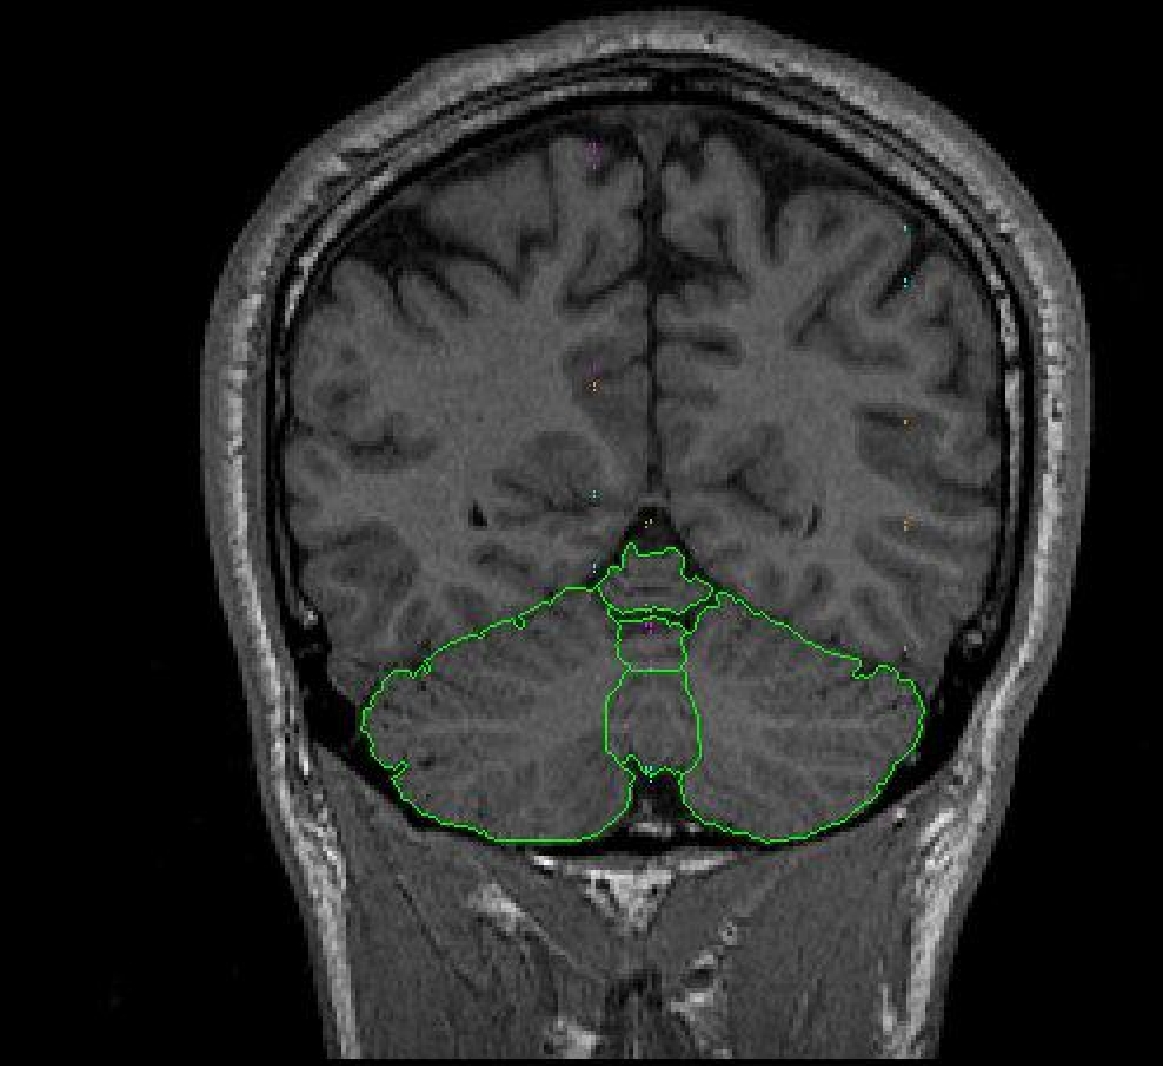

The vermal lobules are segmented into 3 sections including lobules l-V, Vl-Vll and Vlll-X. Sulci lines will be drawn in the sagittal view to determine the borders for the vermal lobules. Lobule l-V is determined by finding the sagittal view containing three distinct sections of the cerebellum. The top most anterior section includes lobules l-V. Lobules l-V are determined by all structures lateral to the primary fissure.

Part IB- Vermal Lobules Vl-Vll

The vermal lobules Vl-Vll are determined by drawing sulci lines in the sagittal

view from the medial aspect of the primary fissure to the lateral aspect of

the prepyramidal fissure.

Part lC – Vermal Lobules Vlll-X

The vermal lobules Vlll-X are determined by drawing sulci lines in the sagittal

view from the lateral aspect of the prepyramidal fissure to the precentral

fissure.

Part llA. – Cerebellar Hemispheres

The cerebellar hemispheres are defined as the areas not included in the vermal

sulci lines.